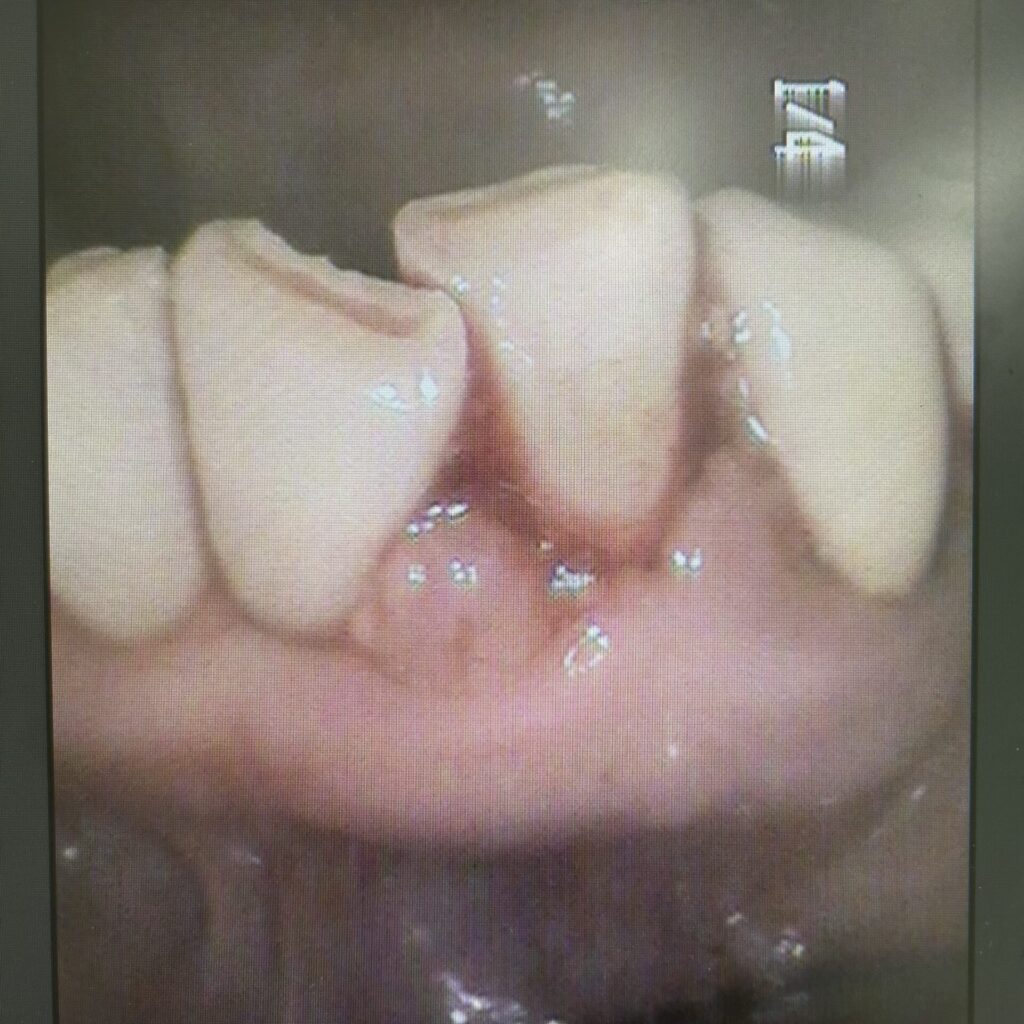

さて、歯肉が腫れてることがお悩みでいらっしゃった患者さんです。

かなり腫れています。全体的にこんな風に腫れていました。

数週間後、ちょっとずつ変化が!!

かなり腫れが引いてきました。

出血も減りました、とのこと。 そして数ヶ月後、現在

本当に同じ歯なのかと疑ってしまうくらい劇的に変化が起きました。

わかりやすいのは、向かって1番右の歯の

被せ物と歯肉の部分です。歯肉が引き締まったことにより境目が鮮明になりました。

これは患者さんの努力の結果です😊本当にがんばりました。